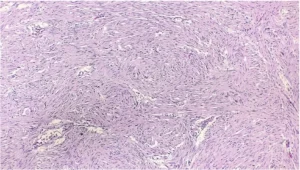

Imagen 7. Tinción HE, 10x.

Células neoplásicas fusiformes, homogéneas, en un patrón fascicular y levemente arremolinado.